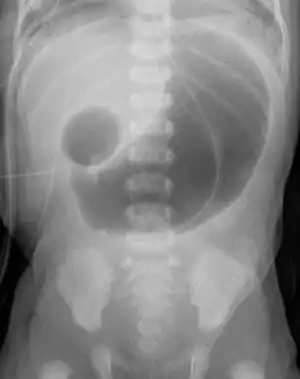

Complication of ileal atresia, meconium peritonitis, in which the bowel perforated before birth. X-ray shows meconium pseudocyst.

Prognosis is usually good if treated with surgery in infancy. The main factor in mortality is the availability of care and appropriate parenteral nutrition after surgery until the bowel can resume normal function.[1]

The most common complication is pseudo-obstruction at the site of surgery due to pre-existing intestinal dysmotility. This can usually only be treated by non-surgical methods.[1]

If the atresia is not treated, the bowel may become perforated or ischemic. This can lead to abdominal tenderness and meconium peritonitis, which can be fatal.[1]